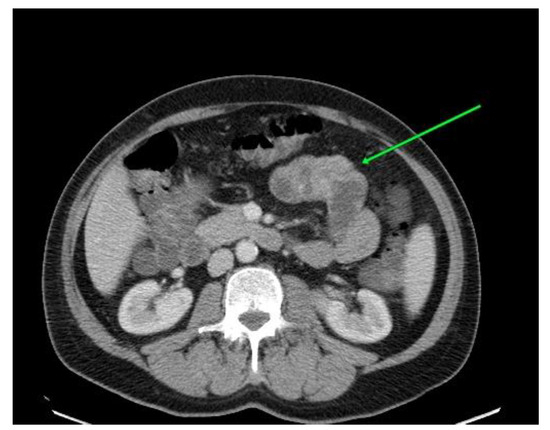

Case Presentation